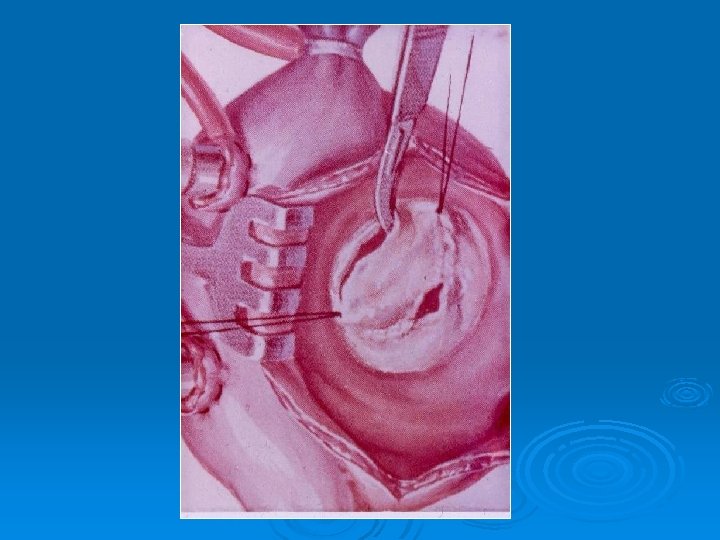

Этап операции протезирования клапана сердца